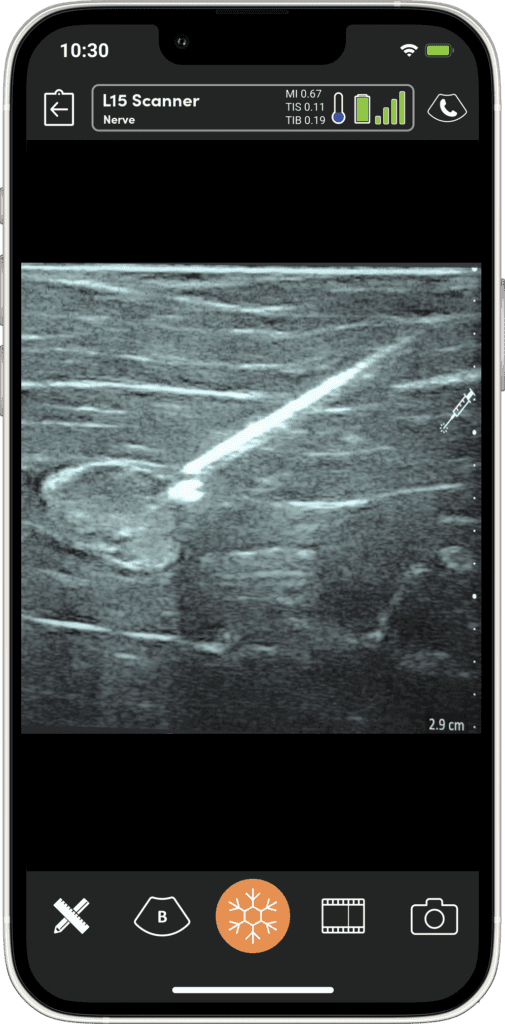

It gives me the confidence that I’m actually hitting the structures that I’m intending to hit.”

I see myself with patients being able to begin to give them answers a little bit quicker… but more importantly to confirm my own diagnostic assumptions or predictions”